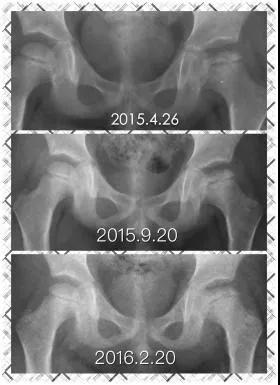

Perthes病即儿童股骨头特发性缺血性骨软骨病,于1910年被Legg、Calve、和Perthes三位学者总结报道,因此也称为Legg-Calve-Perthes病,简称LCPD。发病早期,患儿往往出现跛行和患侧大腿中下段的疼痛不适、有时甚至是健侧膝盖周围疼痛,休息几天就可以缓解。但由于儿童天性活泼好动,上述症状常常容易复发。因此好多孩子常常被家长乃至初诊医生忽视、只是简单认为是“滑膜炎”、“缺钙”或者所谓“生长痛”,没有早期发现并且及时确诊、科学施治,而遗留了头臼曲率适应不佳、髋臼覆盖不良、股骨近端形态异常等等生长发育畸形(图1),导致髋关节出现软骨磨损继而早发骨性关节炎,从而严重影响日常生活和工作。而如果能够早发现早治疗,LCPD完全可以获得优良结果乃至正常髋关节状态(图2)!

图1 LCPD影像学表现,股骨头变形,髋关节覆盖差